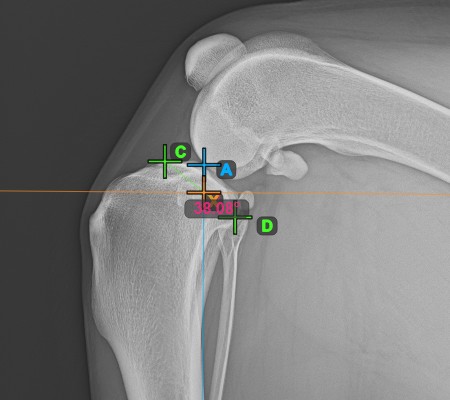

Complete the TPA Angle measurement by marking the most caudal point of the tibial head (tibial plateau). The TPA Angle is automatically calculated as the angle between the line connecting the two points on the tibial plateau and the perpendicular line to the long axis of the tibia.

The image below depicts the usual placement of the most caudal point on the tibial plateau and the automatically calculated TPA Angle measurement.